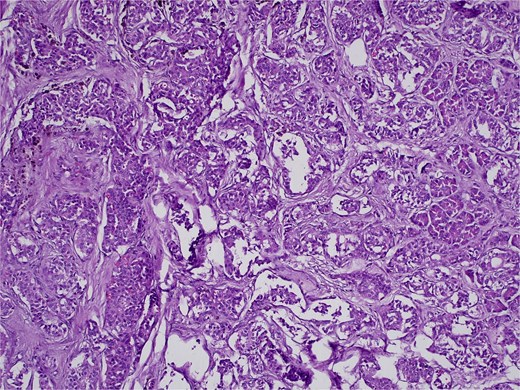

On 27 January 2025, the patient underwent a Whipple procedure (pancreaticoduodenectomy). The surgery included cephalic pancreatectomy with reconstruction through hepaticojejunostomy and gastrojejunostomy in a Roux-en-Y configuration. Gross pathology revealed a firm, white-yellow, indurated mass in the pancreatic head measuring 3.7 × 3.5 × 3 cm with irregular borders and central hardness (Fig. 4). Histopathological analysis confirmed a Grade 1 neuroendocrine tumor (insulinoma), with a Ki-67 index of 2%. The tumor showed direct extension to adjacent pancreatic tissue, the duodenal muscularis propria, the adventitia, and the muscularis of the common bile duct. Five peripancreatic lymph nodes were dissected, three of which were positive for metastases (Figs 5–9).

H&E stain, 100× magnification. Papillary and trabecular architecture with minimal atypia and characteristic “salt and pepper” chromatin.